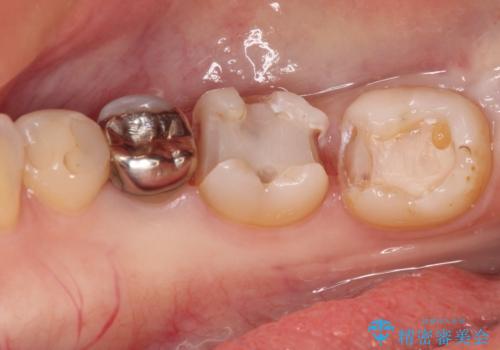

- 奥歯の虫歯を心配して来院した患者様です。

レントゲン写真から、以前治療した詰め物の下に虫歯があることがわかりました。

精度が高く、虫歯の再発リスクの低いゴールドインレーで治療を行うこととしました。